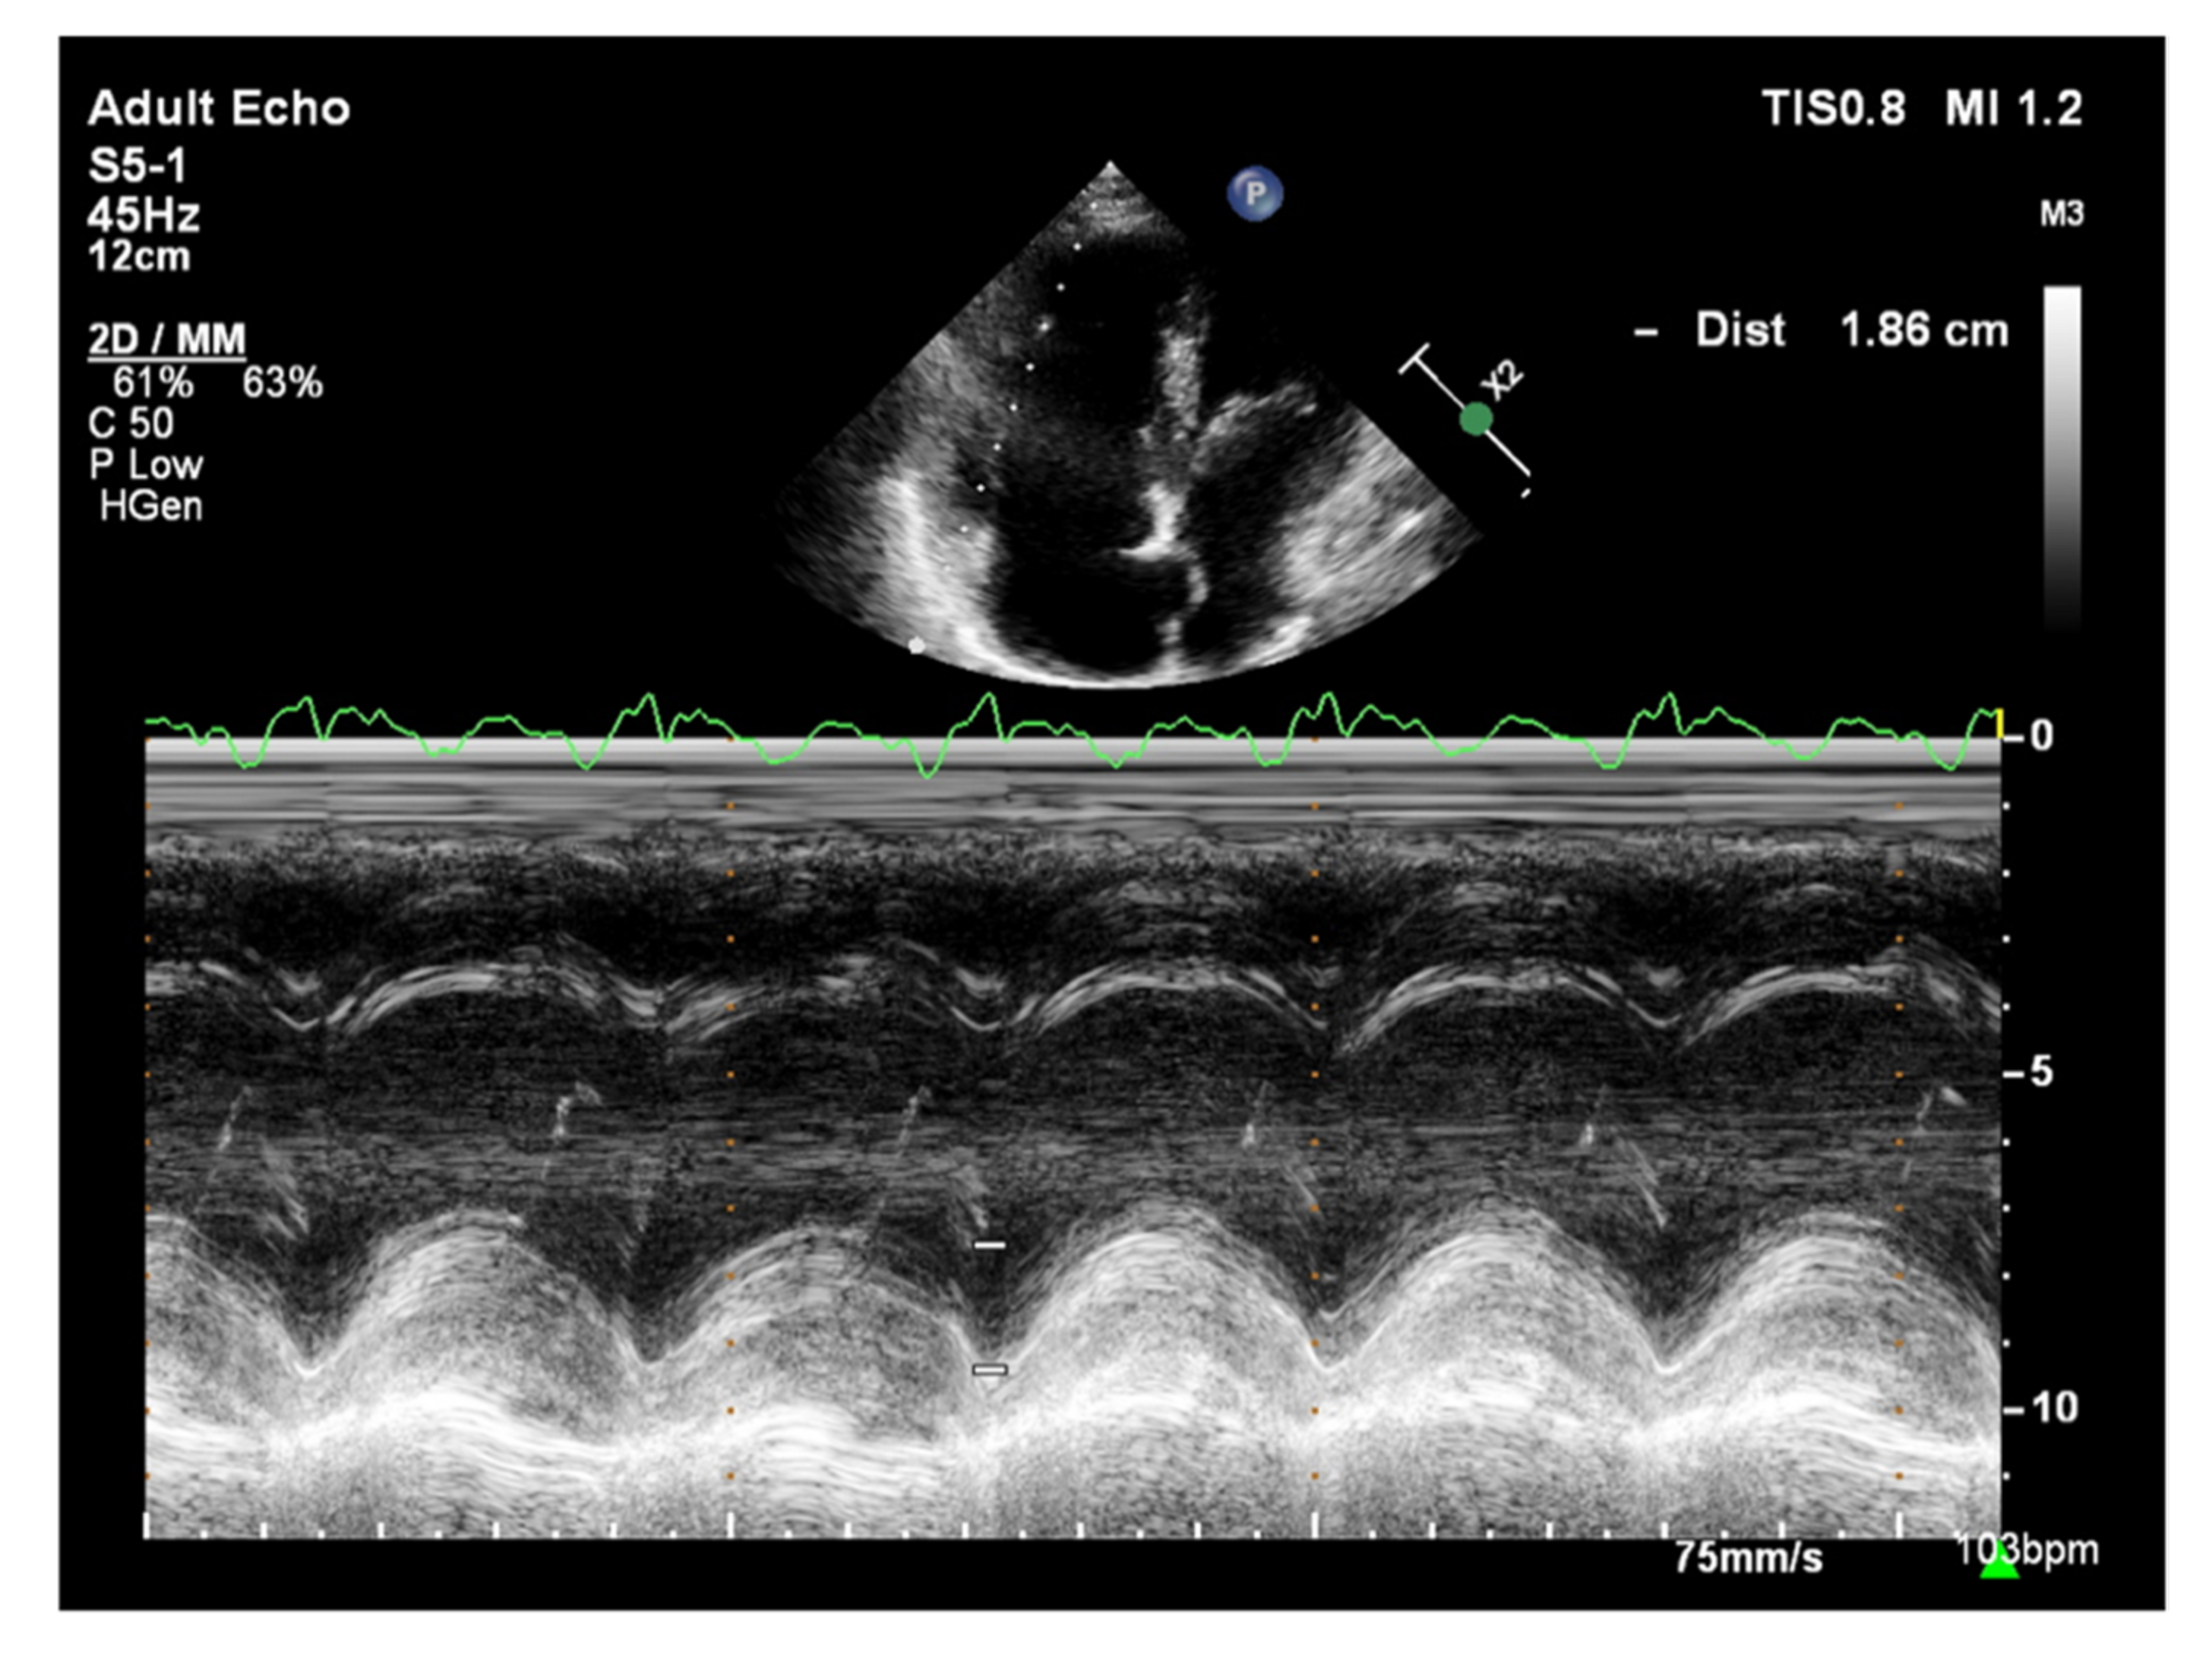

The longitudinal fibers of the right ventricular muscle are mainly responsible for muscle contraction. Contraction of these fibers also causes movement of the tricuspid valve annulus, which moves toward the ventricular apex in systole and toward the atrium in diastole [37]. Therefore, the amplitude of tricuspid annular systolic motion (TAPSE), obtained by the M-mode technique from the 4CH view, reflects RV systolic function (Figure 8) [37]. TAPSE values <18 mm are associated with poor prognosis and higher mortality in patients with PAH [38]. A correlation between TAPSE and RV ejection fraction (RVEF) measured by radionuclide angiography has also been demonstrated [39]. Considering that the TAPSE measurement is uncomplicated, highly reproducible, has little dependence on image quality, and has a high prognostic value, it is recommended that TAPSE is determined in all patients with PAH to assess RV systolic function [2]. However, TAPSE has a disadvantage of being angle-dependent and may be overestimated with apical rocking [40]. In addition, TAPSE may be load-dependent [41].

Figure 8.

Patient with PAH, TAPSE = 1.86 cm. TTE, M-mode. PAH: pulmonary arterial hypertension; TAPSE: tricuspid annular plane systolic excursion; TTE: transthoracic echocardiography.